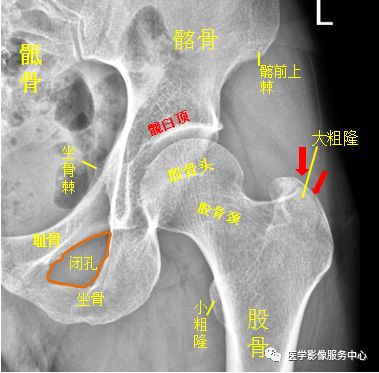

髋关节

左侧股骨大粗隆处见不规则透亮线影,骨折处无明显分离、移位。左侧股骨大粗隆骨折。踝关节